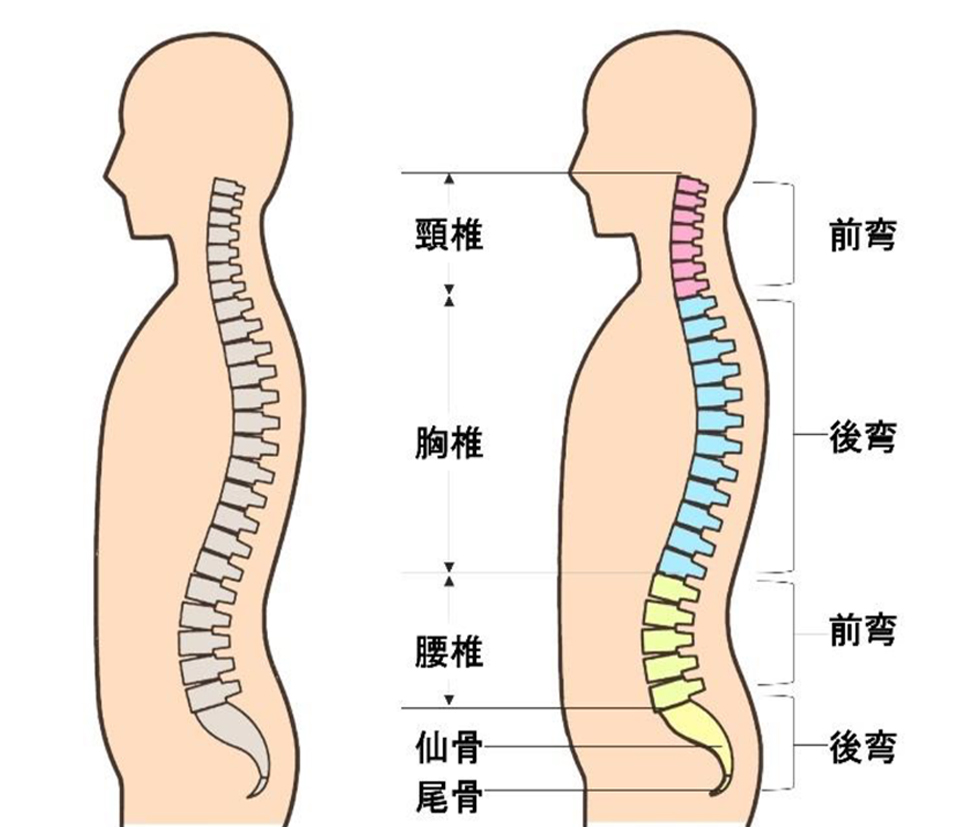

人は首から腰までに脊柱(脊椎)とその周りを支える靭帯、筋肉によって形成されています。脊椎は頸椎、胸椎、腰椎、仙骨、尾骨の5つに分けられます。

脊椎は横から見ると、頭は前方へ、お尻の部分は後方に湾曲したS字カーブをえがいています。脊椎のS字カーブがバランスをとっているため、首への荷重の負担が減り、痛みが出にくい身体を作れています。